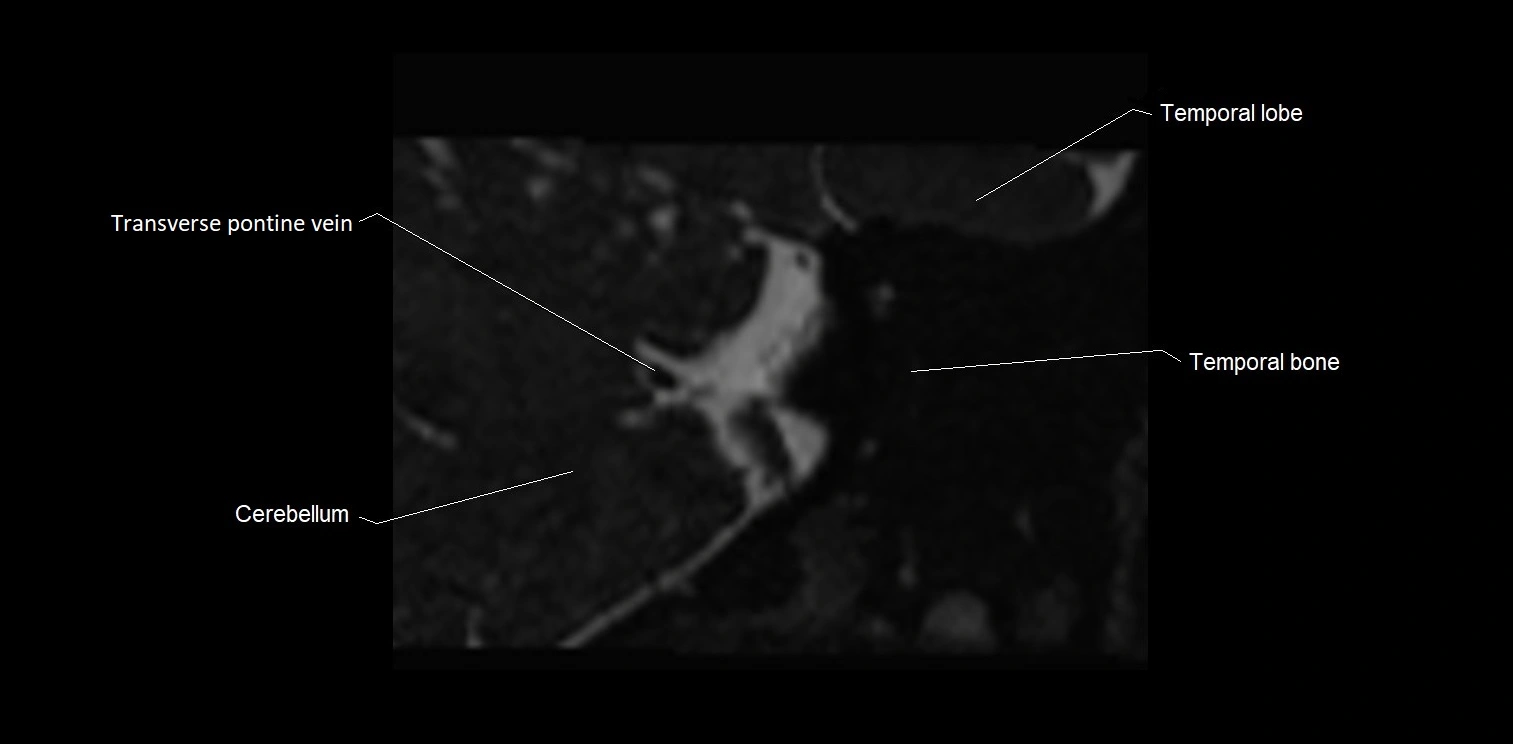

MRI images

image